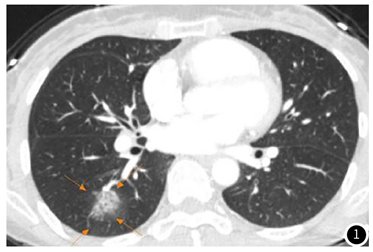

图1 肺内有磨玻璃样结节,周边边缘不清晰

磨玻璃结节(ground-glassnodule, GGN)是肺内有局灶性云雾状密度增高影,包括边界清楚和不清的病变,但能显示出其中的血管和支气管纹理,这一典型的胸部CT影像称为磨玻璃结节,就像在肺组织上蒙了一块磨玻璃一样。病理表现为肺泡壁增厚,肺泡腔塌陷,含气量减少,出现细胞、渗出液及组织碎片。根据是否含实性成分,将GGN分为纯磨玻璃结节(pGGN)和伴有实性成分的混合磨玻璃结节(mGGN)。